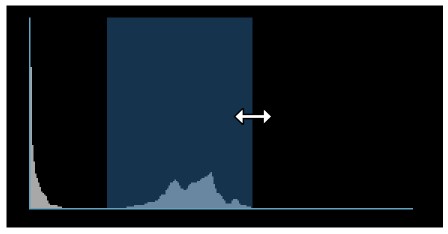

Histogram¶

A windowing histogram is a graphical representation of the distribution of intensity values in an image. It displays the number of pixels at each intensity level, allowing users to adjust the brightness and contrast by setting a window around a range of intensity levels. By adjusting the position and width of the window, the user can optimize the image for their specific needs and better visualize the image features.

To change the window width, press and drag the left or right edge of the rectangular area representing the window.

To change the position or the window center, press and hold on the rectangular area and drag in the desired direction.